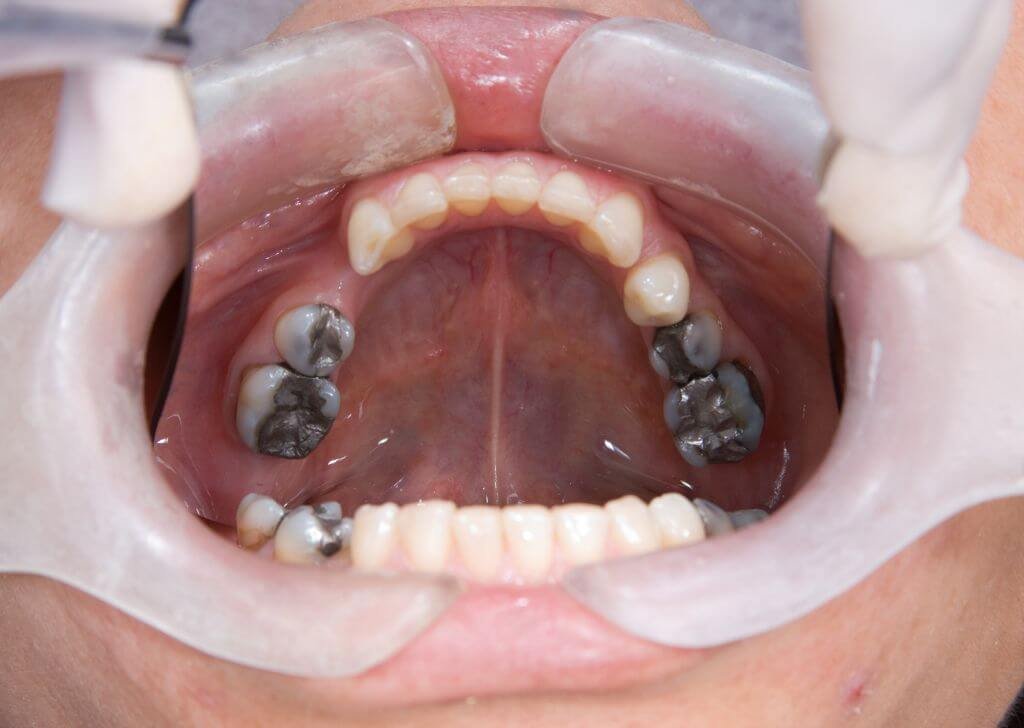

- Karies gigi – Kawasan sukar dicapai oleh berus gigi menjadikan gigi bongsu dan gigi bersebelahan lebih mudah mendapat kaviti.

- Tekanan terhadap gigi bersebelahan – Gigi bongsu yang tumbuh ke sisi boleh menolak gigi di hadapannya, menyebabkan kesesakan dan perubahan susunan gigi.